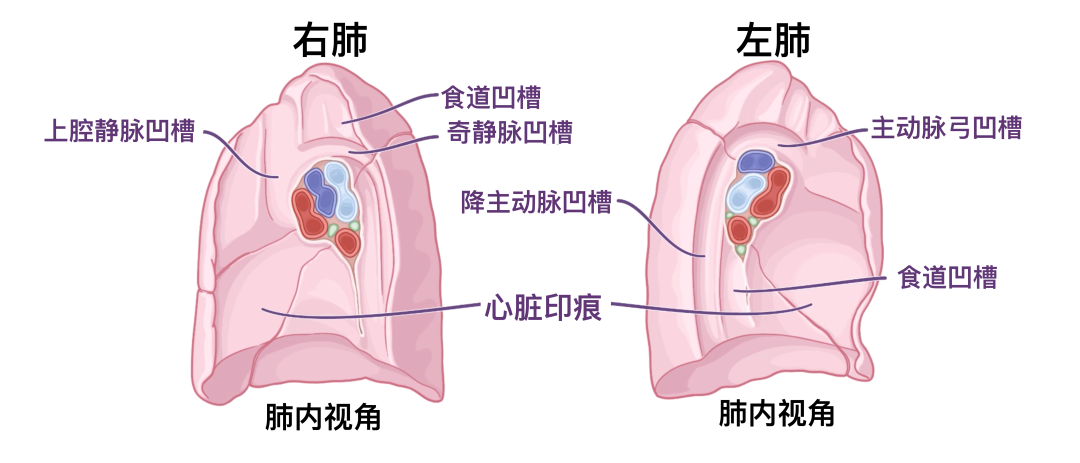

在经过防腐处理的尸体上,肺部纵隔表面可以看到几个压痕。在右肺上,有一个用于食道和奇静脉弓的凹槽,因为奇静脉弓形高于肺门,流入上腔静脉,这也可能导致右肺出现凹槽。两个肺也都有心脏的心脏印记,其中左肺的心脏印记要大得多,因为心尖指向左侧。左肺还将有一个连续的主动脉弓凹槽,以及降主动脉和较小的食道区域。